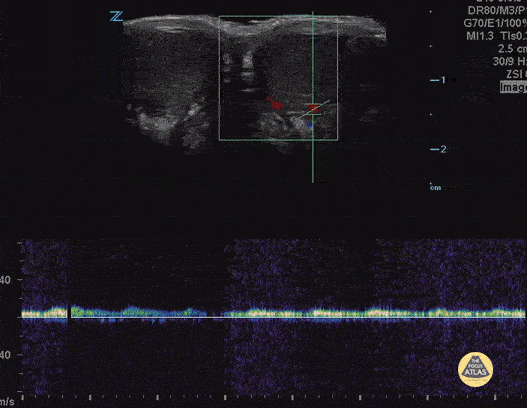

13 yo male presents with intermittent testicular pain. There was some flow to testicle, but when examining spermatic cord flow was twisted (corkscrew sign) indicating partial torsion. Contributor: Paul Khalil, MD and Joshua Kim, DO